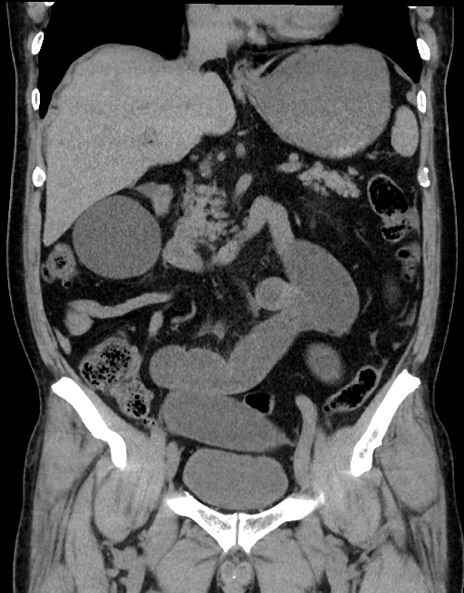

症例15(冠状断像)

【症例】70歳代男性

【主訴】腹痛

【現病歴】今朝から腹痛あり。全体的に痛い。特に左上の方。排ガスが今日はない。冷や汗が出る。

【既往歴】直腸癌術後

【身体所見】左側腹部〜上腹部に圧痛あり。腹膜刺激症状明らかなではない。軽度反跳痛。左下腹部に術後瘢痕あり。

【データ】WBC 7700、CRP 0.02